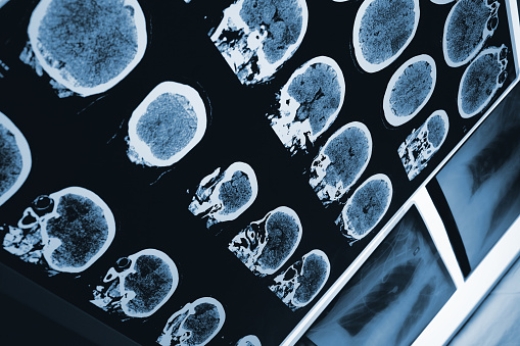

It’s important to keep your brain healthy, especially as you age. Mental decline is one of the most common symptoms of aging and it inflicts most, if not all, elderly people. With the elderly population on the rise, it’s important to promote a healthy brain. Most people get the feeling sometimes that they can’t forget ...click here to read more